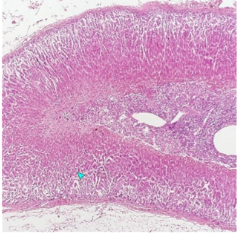

suprerenal gland / adrenal gland

adrenal gland / suprarenal

adrenal gland